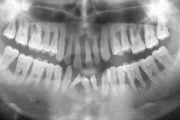

Agressiivse parodontiidi kahjustused rasedal naispatsiendil